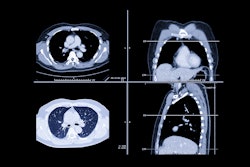

"Despite considerable declines in smoking prevalence during the past few decades, the number of lung cancer deaths attributable to cigarette smoking in the United States is alarming," Islami said in an ACS statement. "This finding underscores the importance of implementing comprehensive tobacco control policies in each state to promote smoking cessation, as well as heightened efforts to increase screening for early detection of lung cancer, when treatment could be more effective."

In 2014, the ACS estimated that 42% of all incident cancer cases and 45% of all cancer deaths in the U.S. could be due to adjustable risk factors. Islami and colleagues conducted this study as an update, estimating the proportion and number of cancer cases and deaths that could be credited to these types of risk factors overall and for 30 cancer types using 2019 data from the Centers for Disease Control and Prevention's National Program of Cancer Registries and the National Cancer Institute's (NCI) Surveillance, Epidemiology, and End Results (SEER) program (they did not use 2020 data due to the effects of COVID on cancer screening).

Cigarette smoking had the largest proportion of cancer cases attributable to risk factors in the study population, at 19.3% of all cases; it contributed to 56% of all preventable cancers in men and 40% of all preventable cancers in women. Excess body weight had the second largest "population attributable fraction" (PAF) at 7.6%, followed by alcohol consumption at 5.4%.

By cancer type, the proportion of cases caused by potentially modifiable risk factors ranged from 100% for cervical cancer and Kaposi sarcoma to 4.9% for ovarian cancer. But lung cancer had the largest number of cancer cases attributable to risk factors in both men and women, the group noted.